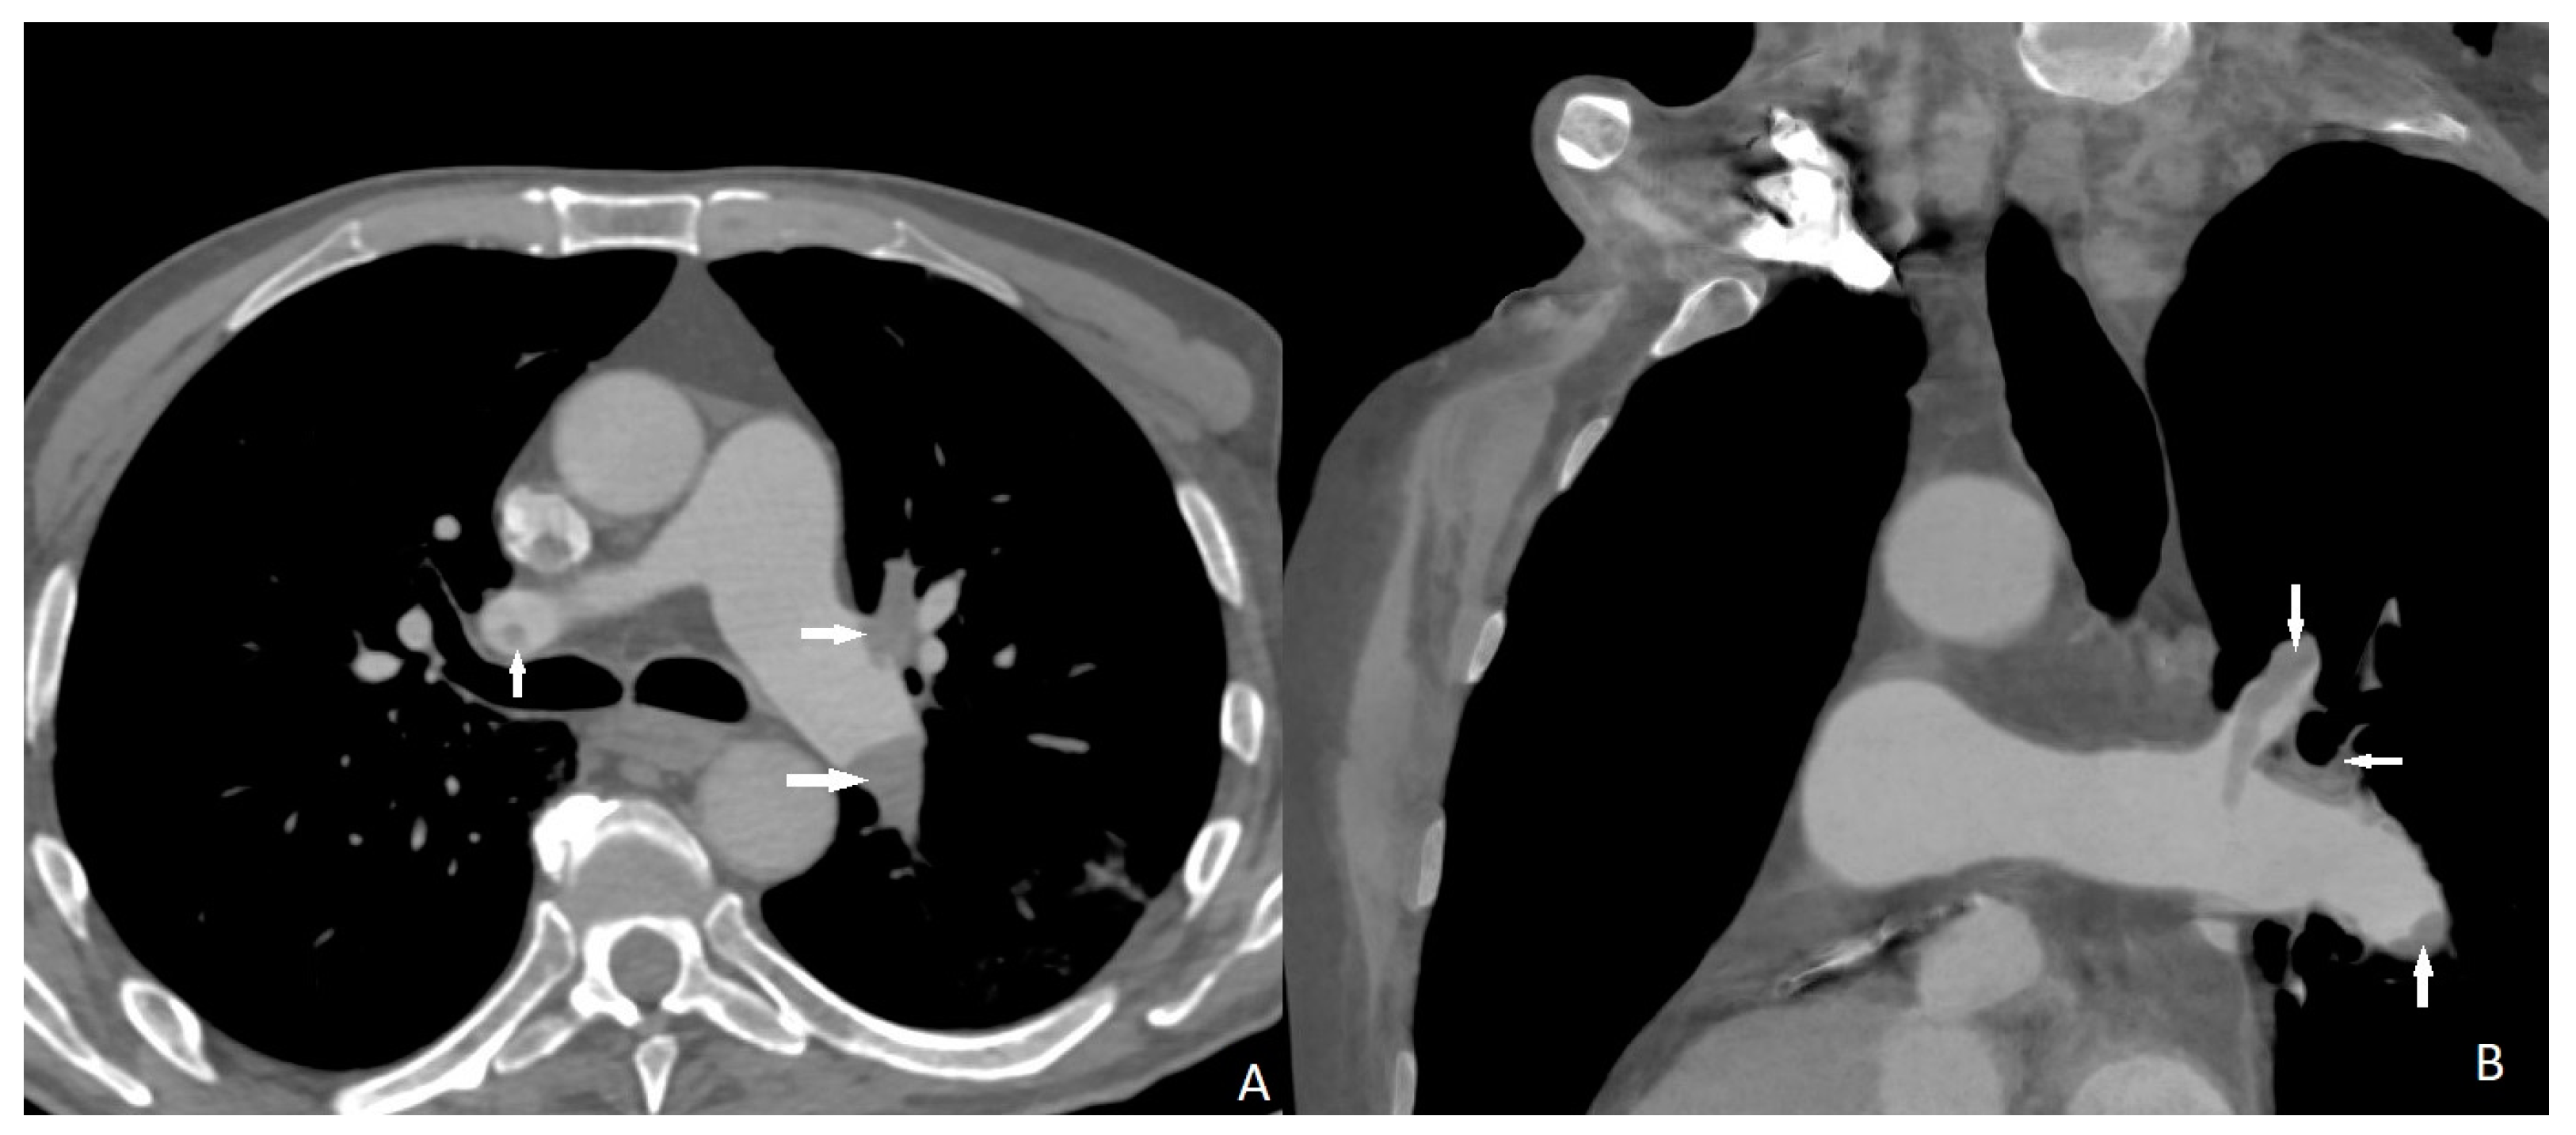

Two cases of distal pulmonary embolism could not be diagnosed with CT scan, and no false positive results were detected (Figure 1). Sensitivity, specificity, and positive and negative predictive values of quadruple-rule-out CT for pulmonary embolism were 93.5% (95% confidence interval [CI] 90–100%), 100% (95%CI 96–100%), 100% (95%CI 97–99%), and 95.3% (95%CI 93–100%), respectively. Cohen’s coefficient of variation (ĸ value) for the presence of pulmonary embolism was 0.95 (almost perfect).

Figure 1.

Filling defects (arrows) on pulmonary arterial phase in the both main and left upper lobar pulmonary artery consistent with pulmonary embolus. ((A) axial; (B) coronal).